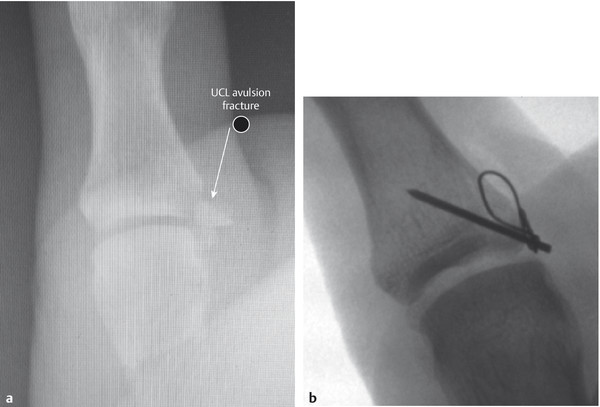

If there is a midsubstance UCL rupture, a direct repair can be performed; however, in some cases Mitek mini anchor repair is warranted. The sequence of repair in both scenarios is illustrated in Fig. 10‑2, Fig. 10‑3, Fig. 10‑4, Fig. 10‑5, Fig. 10‑6, Fig. 10‑7, Fig. 10‑8, Fig. 10‑9, Fig. 10‑10, Fig. 10‑11, Fig. 10‑12, Fig. 10‑13, Fig. 10‑14, Fig. 10‑15, Fig. 10‑16, Fig. 10‑17, Fig. 10‑18, Fig. 10‑19. For an avulsion fracture of the UCL, one must assess the size of the bony fragment. If large, this can be fixed with a tension band K-wire technique (Fig. 10‑20).

Fig. 10.20 (a,b) Tension band wire technique for UCL avulsion with large bony fragment.